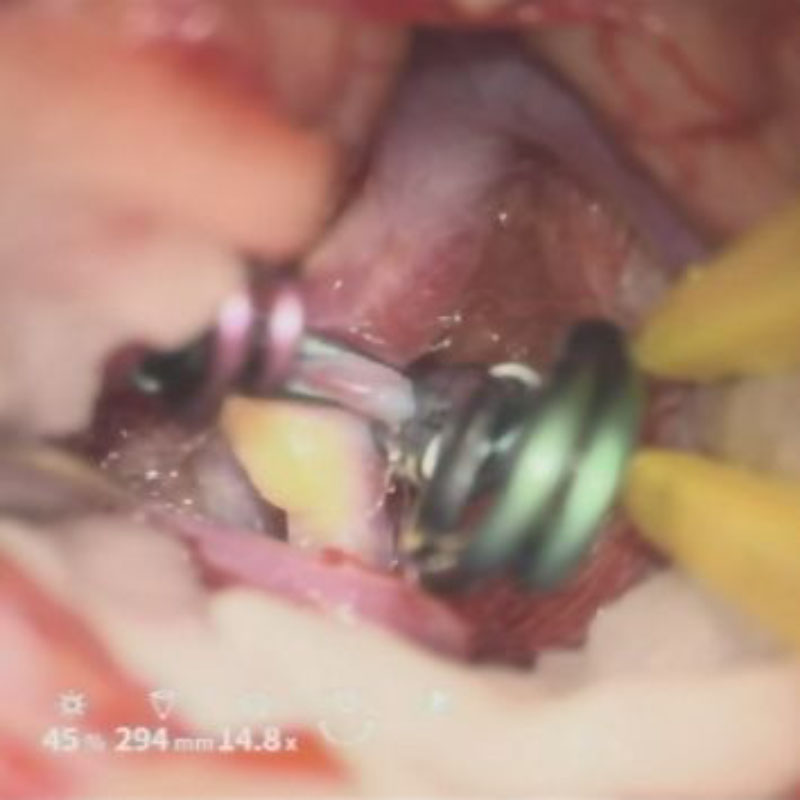

クリップ後